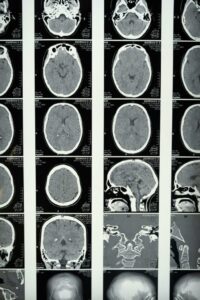

Use in brain imaging

A CT scan is absolutely essential in neurology since it is able to detect any potentially fatal problems in the brain within seconds.

The CT scan is used for:

Diagnosing strokes

Detecting hemorrhages in the brain

Head injuries

Abnormalities

Time plays a significant role when a stroke occurs; hence, it helps to determine whether the stroke is due to a clot or a hemorrhage since the medication for either condition will have an adverse effect on the other one.